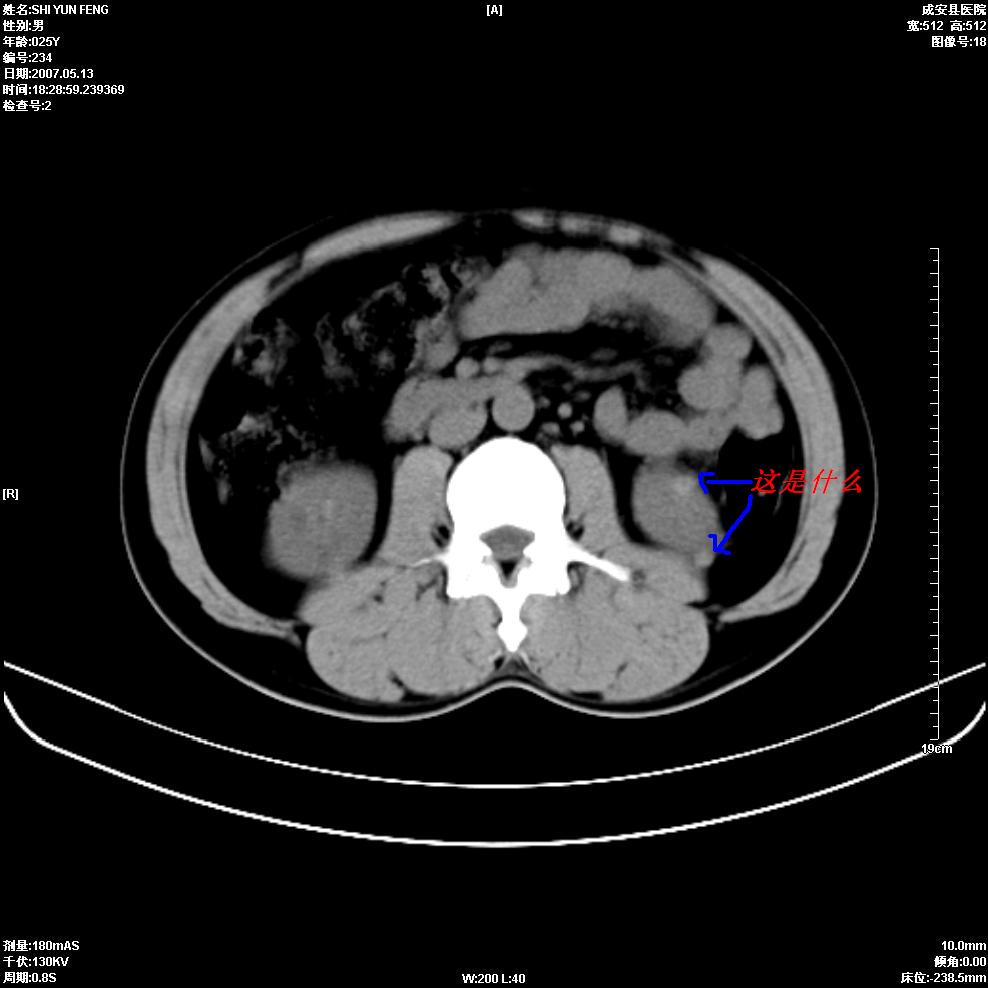

以下是引用zhangzhongshou在2007-5-16 7:36:00的发言:[br]多发性肾囊肿,左肾多发结石。不是多囊肾,楼主箭头所指多考虑左肾囊肿内结石或钙乳,髓质海绵肾不完全除外。[br][br][本贴已被 zhangzhongshou 于 2007-5-16 7:37:18 修改过][br][br][本贴已被 zhangzhongshou 于 2007-5-16 18:15:09 修改过]